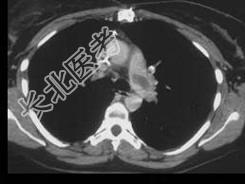

- 单项选择题女,51岁, 心脏手术后,突感胸痛, 结合CT图像,最可能的诊断是 ( )

A、肺栓塞

B、支气管扩张

C、肺水肿

D、肺癌

E、肺不张